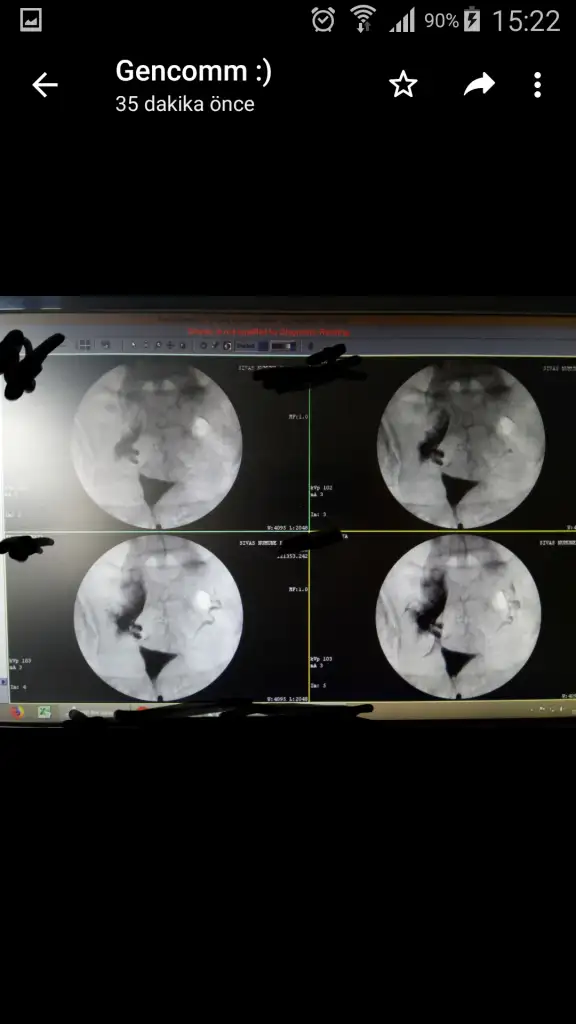

Peki canım bişe daha soracam film görüntüsünde sanki sola yatıklik var gibi bi bakabilir misinizYok canım oluşması için sorun degil kafanı rahat tut. Döllendkten sonrada onu orda tutabilcek ilaçlar verirler zaten

Yok yok o makinenin çekim acısı solda yada sagda degil olmasi gereken yerde canimPeki canım bişe daha soracam film görüntüsünde sanki sola yatıklik var gibi bi bakabilir misiniz